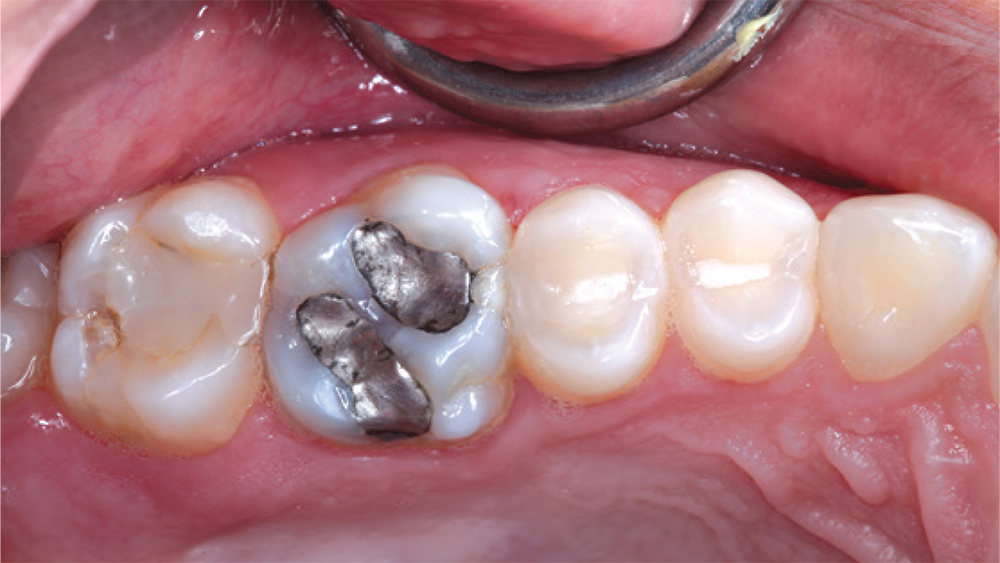

teeth #2

teeth #3

patient's fillings on teeth #2 and #3

In this case, the patient’s fillings on teeth #2 and #3 were removed and the teeth were prepared. During the same appointment, the doctor scanned the patient’s teeth and fabricated onlays from CAMouflage NOW milling blocks using the glidewell.io In-Office Solution. The onlays were delivered following a scientifically validated bonding protocol, maximizing the longevity of the nanohybrid composite restorations.